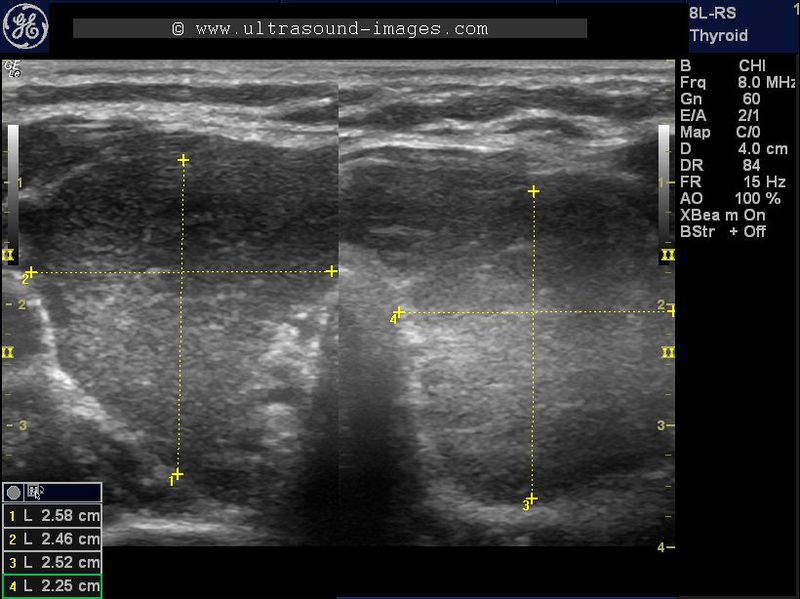

multinodular goitre with embedded carotid artery

In this middle aged female patient, there is a large, primarily cystic goitre involving the left lobe. Multiple septae are present in the cystic lesion of the left lobe of thyroid. However, the interesting feature is the right lobe of thyroid, which actually covers the right common carotid artery,which is partially embedded within the right lobe of thyroid. This is a rare discovery and the first time I have actually seen this variant of this vessel. This finding itself of the right common carotid artery embedded in the right lobe of the thyroid may by itself be just an incidental finding with little significance.

normal thyroid variant

this thyroid shows a small aberration, or normal variant, wherein the right lobe of thyroid surrounds the right common carotid artery. The result is the right common carotid artery is embedded within the right lobe of thyroid. In addition, the left lobe shows a small colloid nodule.